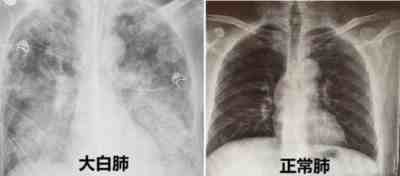

万一家里的老人沉默性缺氧,最后变成了大白肺,重症死亡怎么办?大家都不希望自己的亲人因为没能及时监测到血氧指数,最终变成停尸房里被蓝色塑料袋裹着的冰冷尸体,只能隔着玻璃做最后的告别吧?